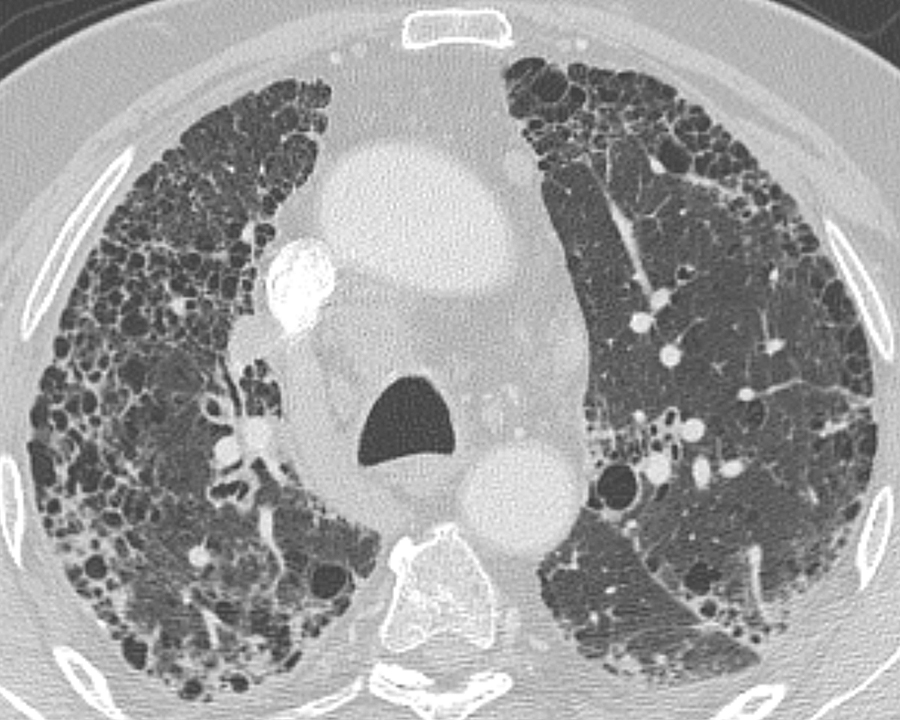

Gallery Pulmonary Fibrosis IPF IPF axial

IPF axial